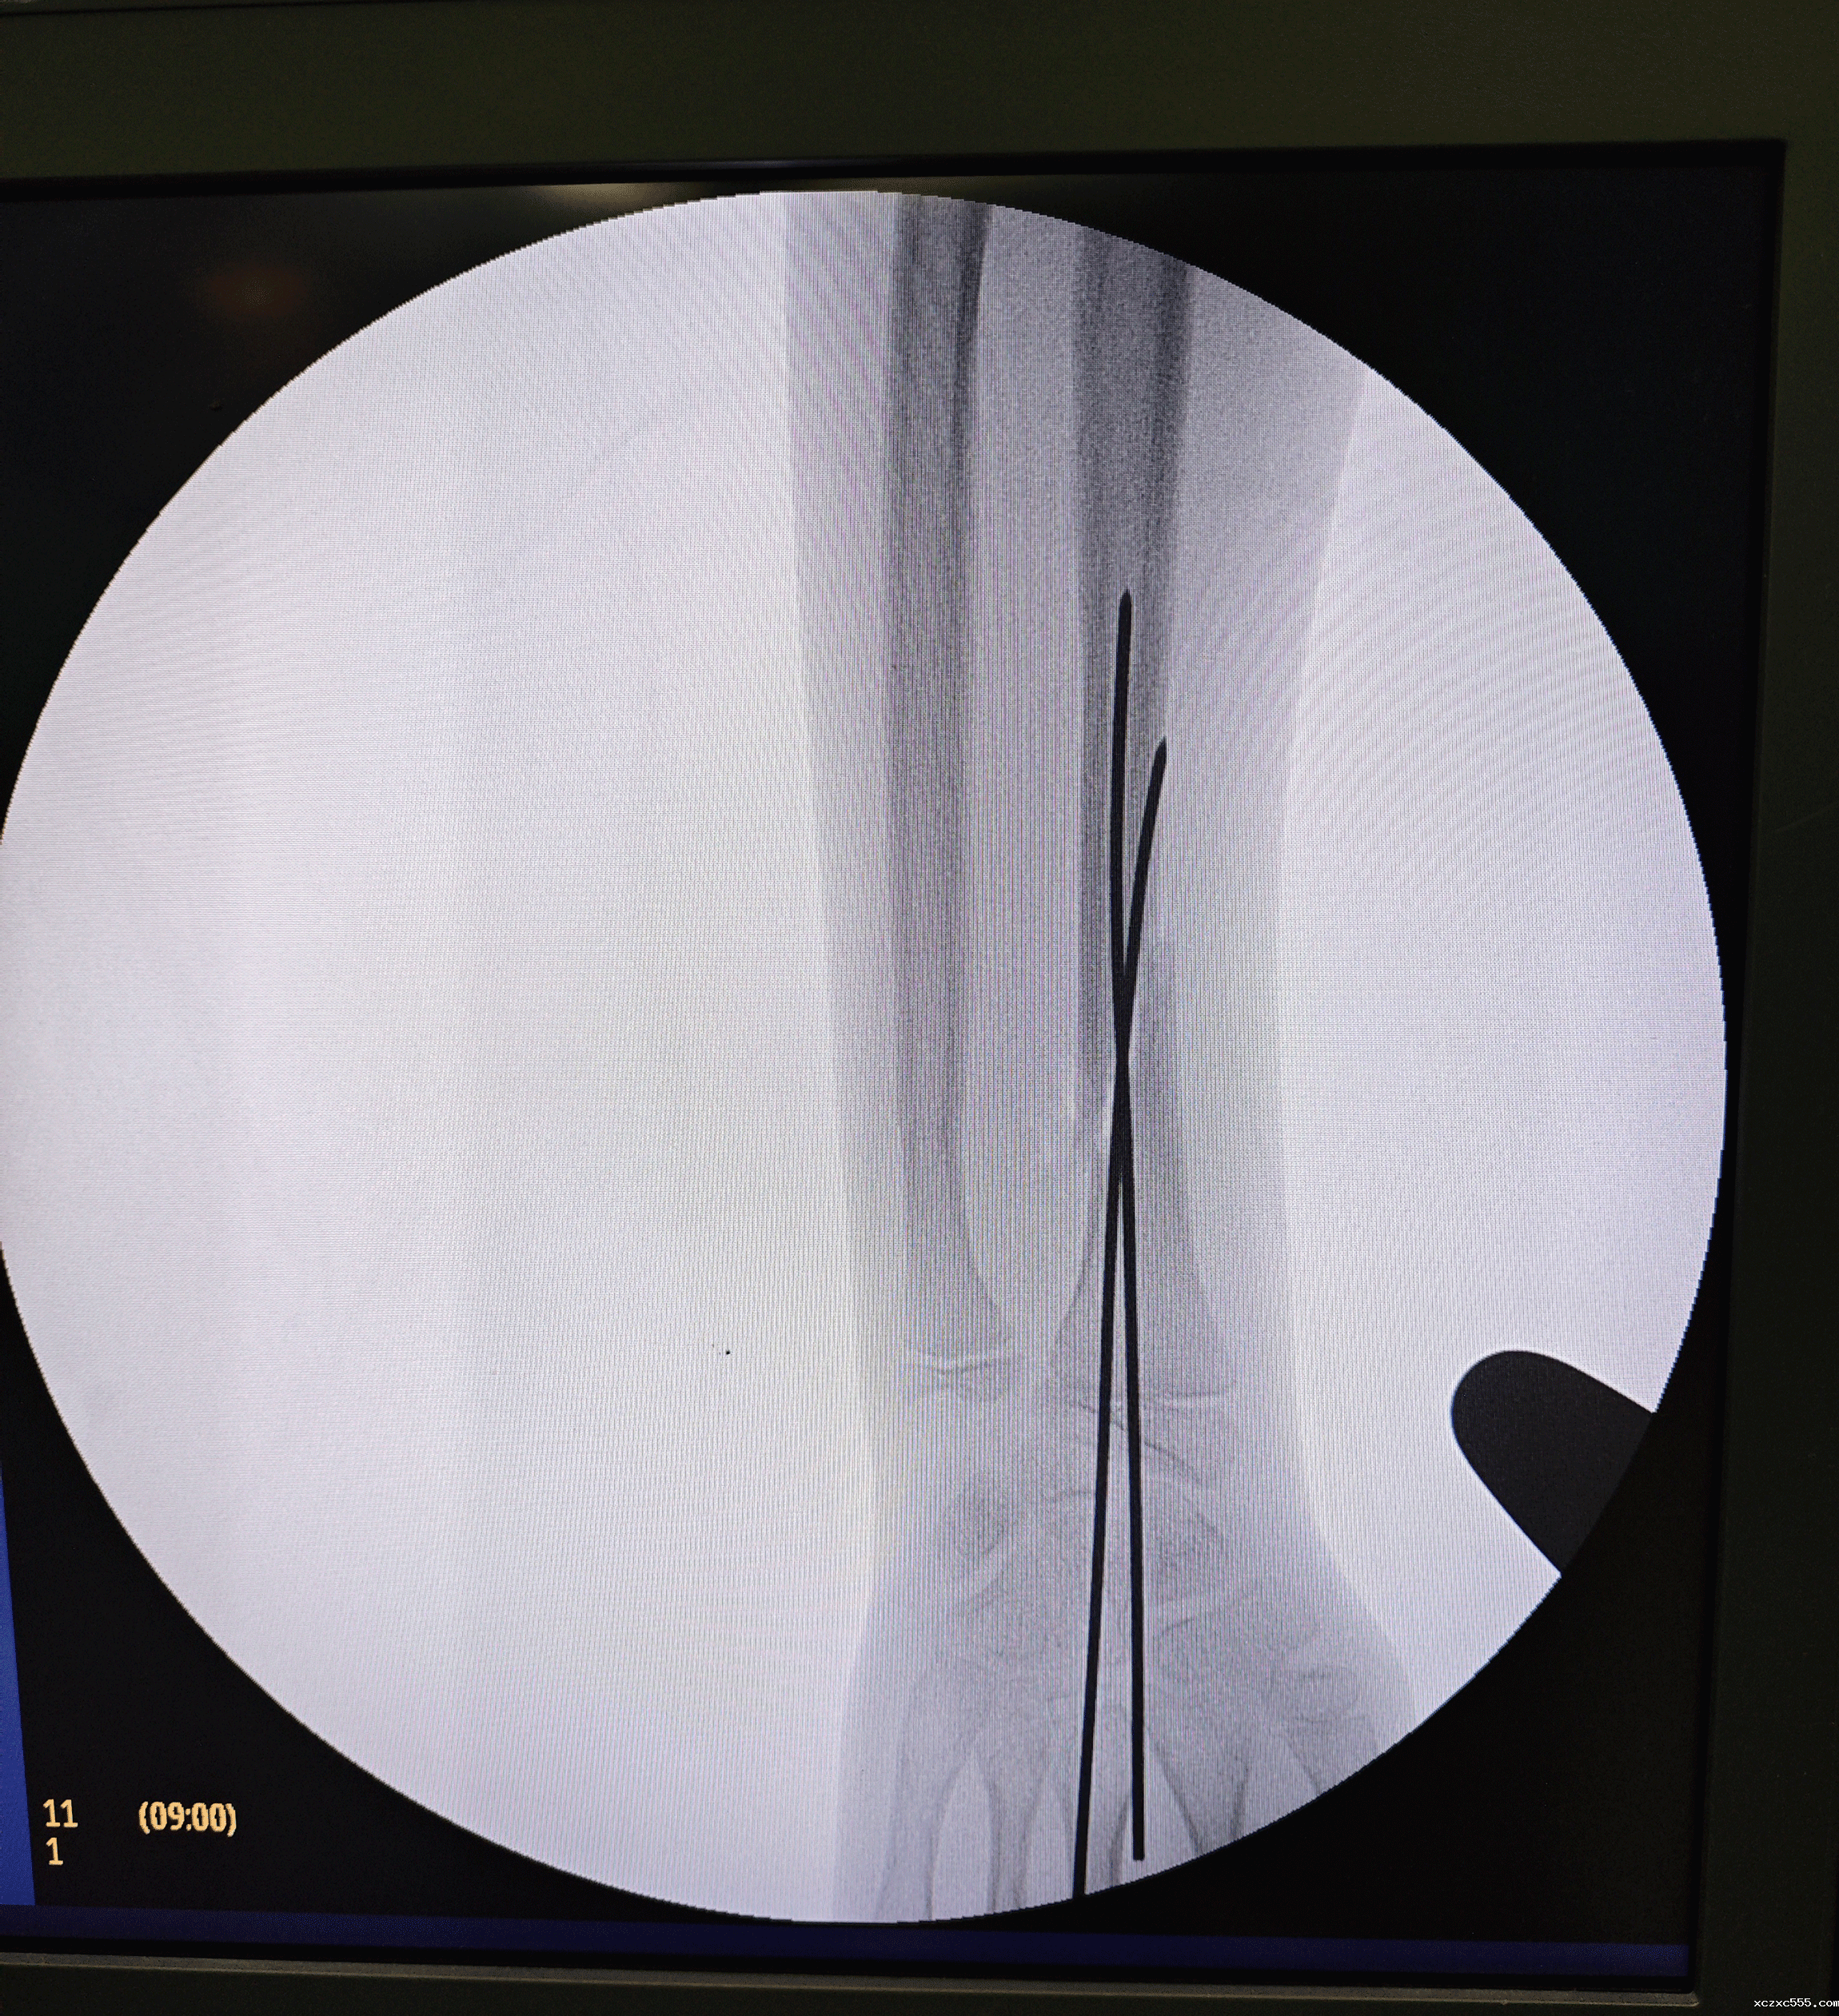

在征得患儿家长同意后,祝振华主任带领小儿外科团队凭借精湛的技术和默契的配合,成功为航航实施了手术。在C臂透视的辅助下,祝振华主任精准牵引了桡骨断端,并使用两枚克氏针进行了微创髓内固定。术中采用了先进的驱血技术,有效减少了术中出血。历时40分钟,手术顺利完成,相比传统的钢板手术,切口微小且美观,针尾留在皮下,避免了患儿日后需要经历二次手术来取出内固定的风险与痛苦。

▲术中使用两枚克氏针进行了微创髓内固定